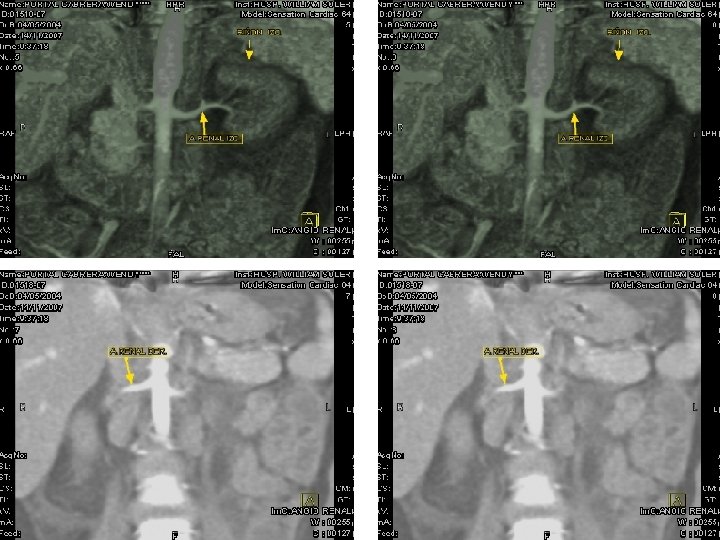

En un estudio de Angiotac Renal contrastada no se observaron zonas de estenosis vasculares llamando la atención el afinamiento de las arterias renales a su entrada a los hilios con escasa captación y excreción del contraste en ambos órganos. Durante la evolución posterior la paciente ha presentado episodios de Peritonitis, cuadros de descompensación cardiovascular relacionados con Pericarditis con efusión y notable hipertrofia miocárdica, especialmente de cavidades izquierdas relacionada con su hipertensión sostenida. Actualmente se encuentra bajo tratamiento de hemodiálisis crónica a la espera de Trasplante Renal.

ANGIOTAC